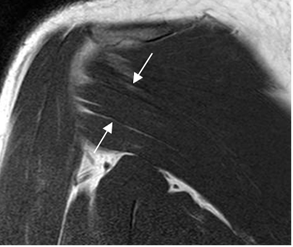

Los tendones de todos los grupos musculares, se aprecian como estructuras hipointensas en todas las secuencias, en relación con los sitios de origen e inserción. (Fig 12 a 17).

Fig 12. Tendón del supraespinoso normal.

A: RM axial en FFE y B: RM coronal en T2. Supraespinoso normal, con inserción en la tuberosidad mayor.

Fig 15. Tendón del redondo menor normal.

RM coronal en T1. Inserción en la tuberosidad mayor.

Fig 17. Tendones normales del manguito rotador.

RM sagital en T2. SE: Supraespinoso. IE: Infraespinoso. SB: Subescapular. RM: Redondo menor. BI: Cabeza larga del bíceps.